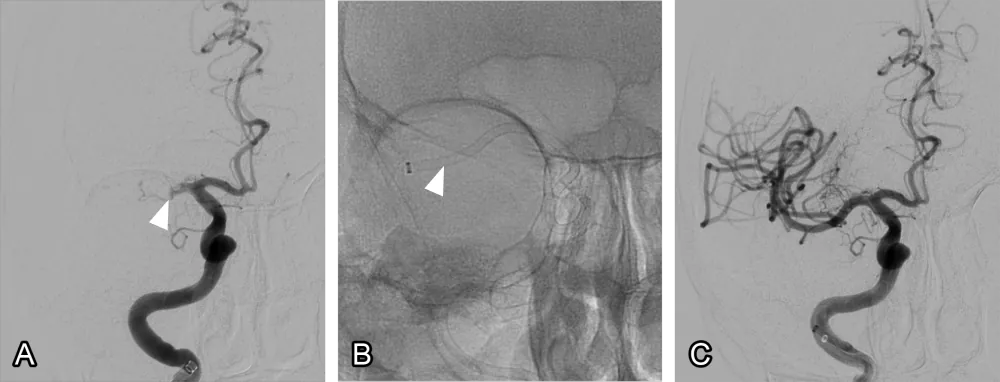

Mechanical thrombectomy is a procedure for removing a blood clot, which is the underlying problem causing the stroke. It involves using a special retrieval device to capture the clot and restore normal blood flow (fig. 1). If the clot is removed before it causes permanent damage, the prognosis usually improves. It’s performed globally in specialist hospitals and is suitable for many, but not all, stroke patients.

Figure 1: Mechanical thrombectomy. (A) The arterial blood flow is obstructed at the arrow by a blood clot. (B) A long tube called an aspiration catheter is inserted into the artery and suction is applied. (C) The clot is sucked out and the blood flow into the smaller arteries is restored.